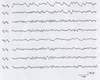

Hypsarrhythmia

seen in patients with infantile spasms

High voltage, irregular slow waves w/ multiple sharp & spike d/cs

Infantile Spasms

1) Describe EEG Findings

2) What syndrome presents with infantile spasms + MR?

3) Name 3 potential underlying etiologies

4) What is most common treatment?

1) EEG: Hypsarrythmia, high voltage diffuse slowing with multifocal spikes and sharps in a chaotic fashion.

2) Often with mental retardation (= West Syndrome)

3) Etiology: Inborn errors of metabolism; structural brain abnormalities; TS

4) Tx: ACTH; (Vigabatrin with TS)